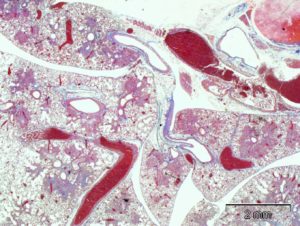

Murine models of Sarcoidosis or granulomatous pneumonia, pulmonary fibrosis and hypersensitivity are important for the assessment of novel therapeutics and diagnostics, as well as for the study of disease pathogenesis. CBI has developed and validated a robust murine model of Propionibacterium acnes-induced hypersensitivity, or granulomatous pneumonia. In this model, the repeated intrapulmonary introduction of killed P. acnes induces a robust, uniform and marked inflammatory response in the lung characterized by inflammation, granuloma formation and fibrosis throughout the lung.

- Histopathology

- Immunohistochemistry and special stains

- Clinical pathology

- Cytokine mediators